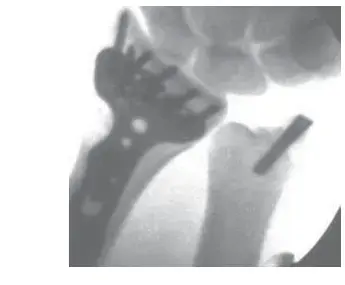

• الأشعة السينية (X-rays):

• على الرغم من أن الأشعة السينية لا تظهر الأنسجة الرخوة مثل الأوتار، إلا أنها يمكن أن تستبعد مشاكل أخرى في العظام مثل كسور الإجهاد أو النتوءات العظمية (bone spurs) التي قد تساهم في تهيج الوتر أو تحاكي أعراض التهابه.